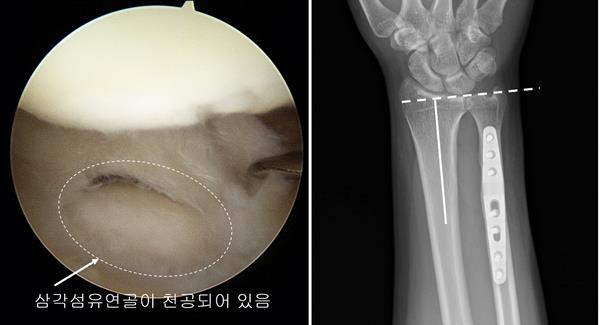

비교적 초기에 진단되면 약물, 주사 치료와 재활 치료를 통해 치료될 수 있으나 가장 중요한 것은 손목 척측의 부하를 줄이는 노력이 필요한데, 손목이 척측으로 꺾인 상태에서 회전운동을 피해야 하며 팔꿈치와 손목 사이의 부분인 전완부 근력운동을 꾸준히 해야 한다. 오래 방치할 경우 손목을 움직일 수 없을 정도로 통증이 심해져 수술적 치료를 피할 수 없다.

이재성 교수는 “테니스, 요가 등 손목을 쓰는 운동을 하면서 통증을 대수롭지 않게 여기다 병이 악화돼 병원을 뒤늦게 찾는 경우를 빈번하게 본다. 관절이 비교적 괜찮으면 척골단축술의 수술로 치료될 수 있으나 이러한 상태가 방치될 경우 연골이 완전히 망가져 관절 자체를 고정하는 수술이 필요하다. 이런 경우 정상적으로 움직이지 못하는 상태가 된다”고 주의를 당부했다.